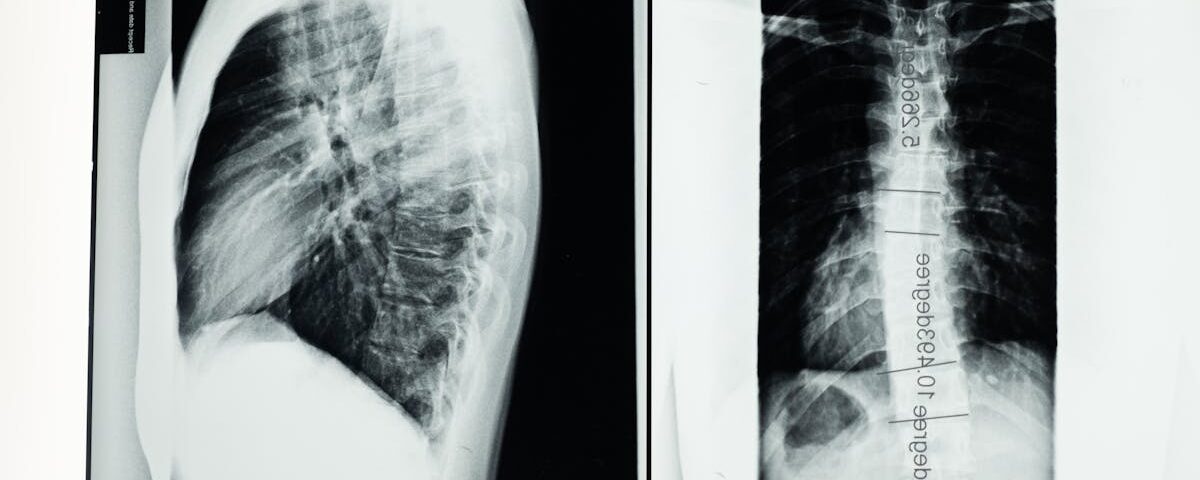

Quels examens sont nécessaires avant de commencer un traitement de décompression pour un disque écrasé?

Une IRM ou une radiographie est souvent recommandée pour évaluer l’état de la colonne vertébrale.

Quels examens permettent de diagnostiquer un pincement discal?

Une IRM ou une radiographie est souvent utilisée pour confirmer le diagnostic d’un pincement discal ou d’un disque écrasé.